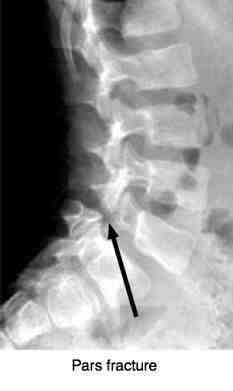

Sacroiliac joint pain, spondylolysthesis, lumbar facet syndrome ...